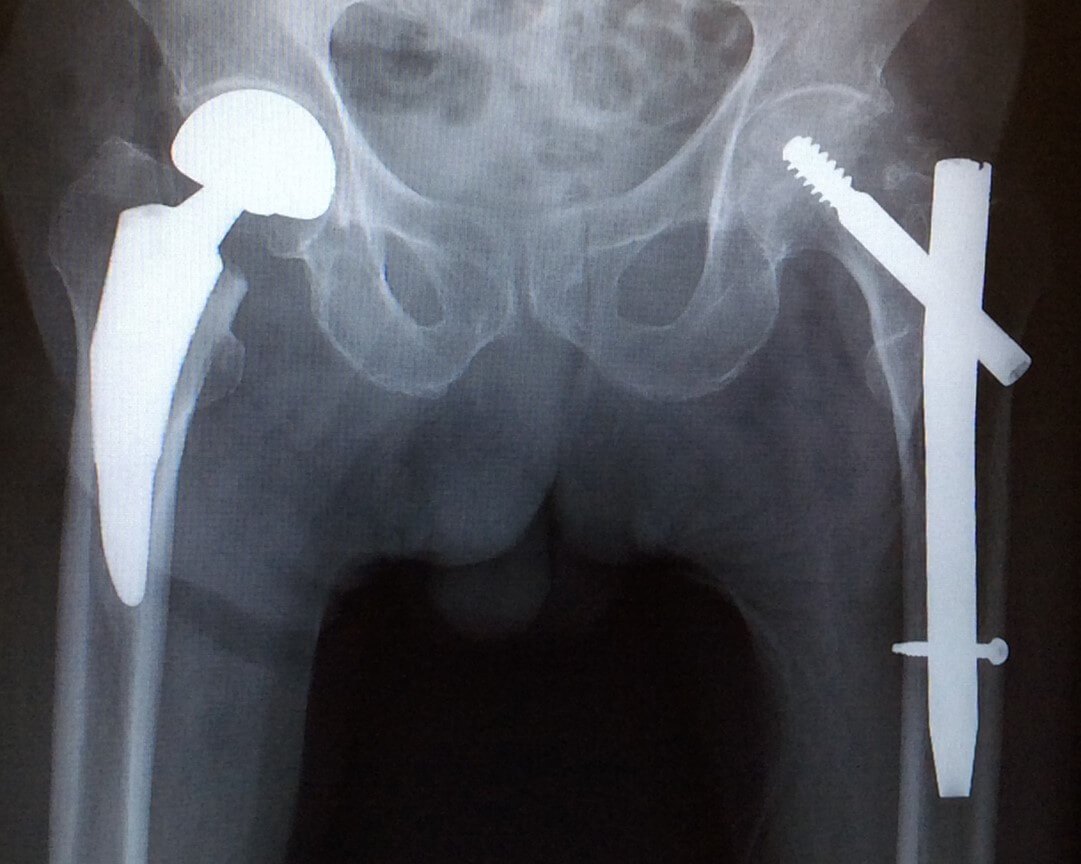

コラム27 人工関節メーカーに伺いました|人工関節コラム|人工関節とは|人工関節ドットコム, 人工股関節置換術と人工骨頭置換術 | 世田谷人工関節・脊椎クリニック,

人工股関節置換術と人工骨頭置換術 | 世田谷人工関節・脊椎クリニック, 人工股関節置換術 MIS について | 人工関節について|湘南鎌倉人工関節センター|人工股関節置換術に特化,

人工股関節置換術 MIS について | 人工関節について|湘南鎌倉人工関節センター|人工股関節置換術に特化, 人工股関節置換術と人工骨頭置換術 | 世田谷人工関節・脊椎クリニック

人工股関節置換術と人工骨頭置換術 | 世田谷人工関節・脊椎クリニック